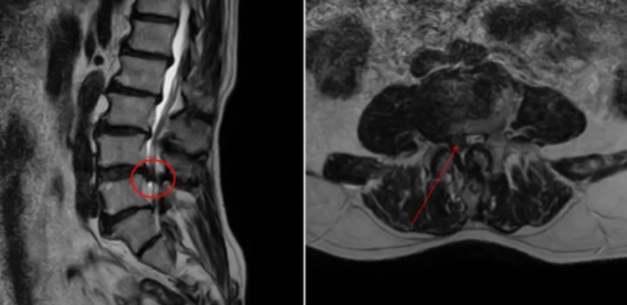

CT显示右侧神经重度狭窄

患者李女士70岁,半年前出现腰痛和右下肢放射痛,走百米左右就得休息,当地医院诊断为腰椎椎管狭窄症,为她进行了口服药物及理疗等保守治疗,但效果一直不太理想。想根治就只能手术,李女士担心手术创伤太大,不愿接受。8月初,李女士病况加重,连下床这样简单的动作,腰腿都痛得受不了。多方打听后,她得知自治区人民医院骨科脊柱二病区可以做微创手术,于是慕名前来。